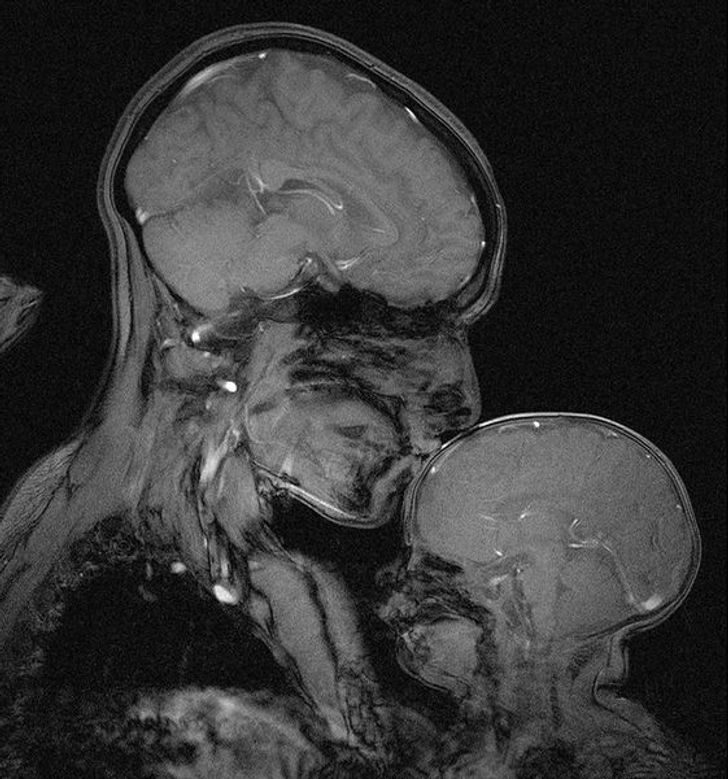

6. Женщина с младенцем в аппарате МРТ